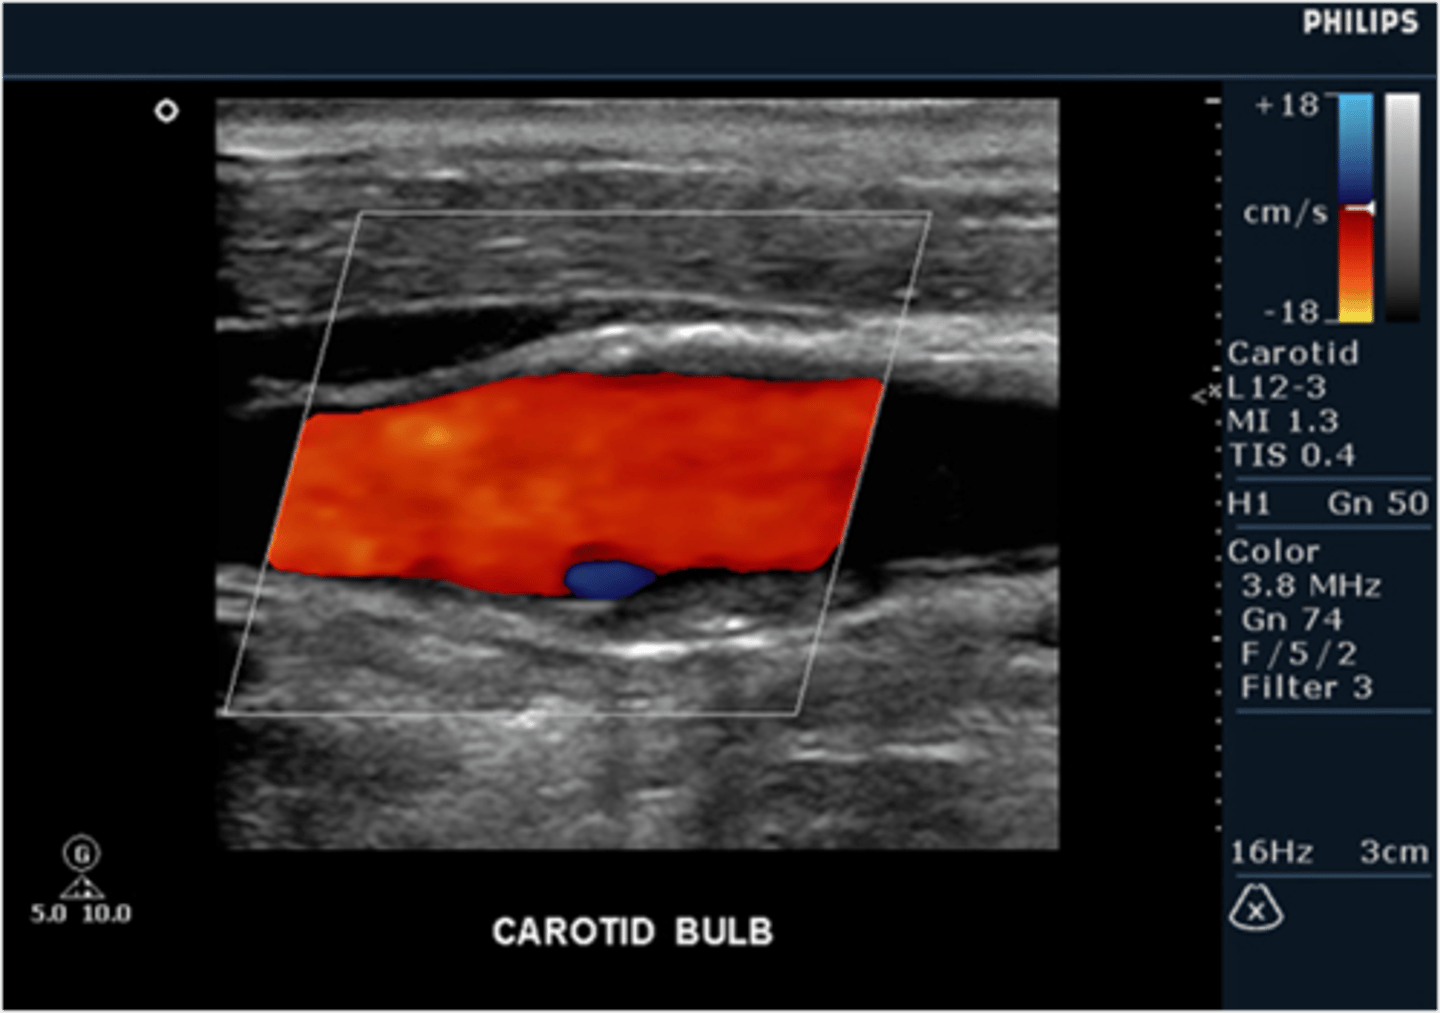

When scanning a carotid artery study on a patient, the sonographer notes a small area of reversed flow as detected by color flow Doppler in the area of the carotid bulb (bifurcation). Should the sonographer report this finding as normal or abnormal?

normal, this is a result of boundary layer separation due to change in flow direction at the bulb